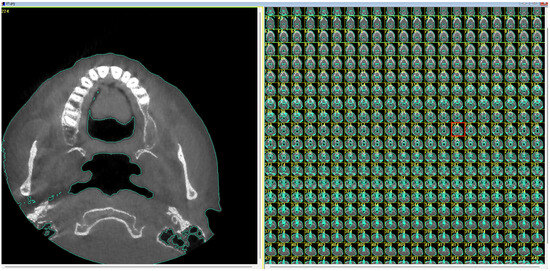

2.1. Digital Modeling

- Generation of the geometric model for CFD numerical analysis from the CBCT image.